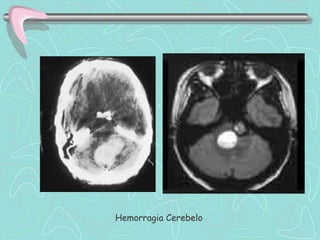

DIAGNÓSTICO

TOMOGRAFÍA COMPUTARIZADA DE ENCÉFALO

•Examen de elección en el Ictus agudo

ICTUS HEMORRÁGICO

•Lesión Hiperdensa que ocupa espacio y desplaza en

diverso grado el parénquima cerebral.

•En HSA puede ser poco hiperdensa, de ubicación

extraparenquimal, e invadir ventrículos cerebrales.

Las Neuroimágenes informan sobre el tipo de lesión, su

tamaño, localización, distribución vascular; la presencia de

complicaciones, y también sobre la necesidad de manejo

quirúrgico.

Hemorragia Cerebelo